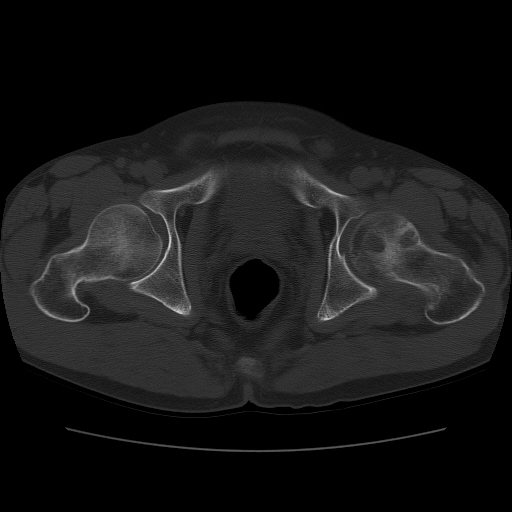

标题: CT11650:左髋病变,请会诊.

左髋疼痛不适近半年,局部无红肿热.无明确外伤病史.黄酒每天二餐.

考虑左侧股骨头缺血性坏死.(常期饮酒引起代谢障碍?)

左侧股骨头缺血性坏死;很典型。

“局部无红肿热.无明确外伤病史.黄酒每天二餐”。考虑左侧股骨头缺血性坏死。